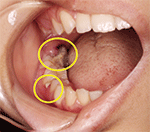

図❶ 下顎右側臼後部舌側歯肉、ならびに

65歯間乳頭部に一部壊死化した組織を認めた

口腔内所見:下顎右側臼後部に限局した接触痛を伴う歯肉腫脹を認めた。下顎右側臼後部舌側ならびにrd65歯間乳頭部に一部壊死組織を認めた。壊死組織の周囲に硬結は触知せず、あきらかな排膿所見は認めなかった(図❶)。